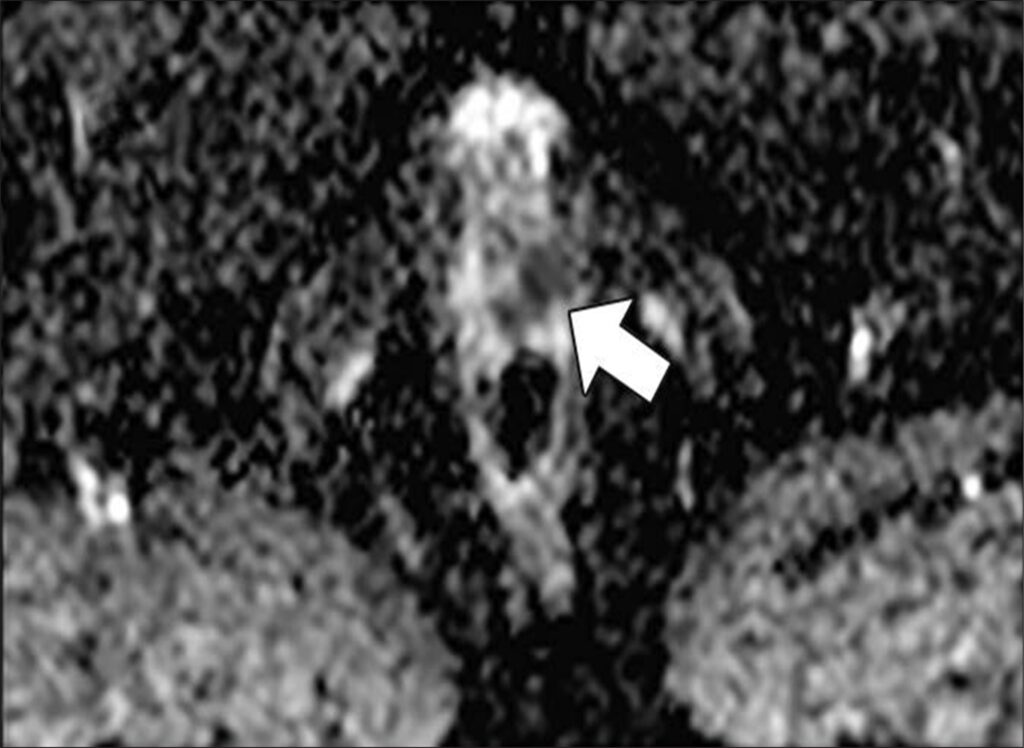

47-year-old man with history of two negative systematic biopsies at another facility and increasing PSA level (most recently, 35.6 ng/mL). Multiparametric MRI was performed for persistent clinical suspicion of clinically significant prostate cancer

Top to Bottom: Axial T2-weighted (Top), axial high-b-value (2000 s/mm2) (Middle), and calculated ADC (Bottom) MR images show left apical anterior central gland lesion (arrow) with very high suspicion of being clinically significant prostate cancer. Lesion is PI-RADS category 5. MRI–transrectal ultrasound fusion biopsy of lesion resulted in pathologic diagnosis of prostatic adenocarcinoma, Gleason 4 + 3 = 7 (grade group 3). Gleason 4 pattern represents 60% of tumor. Prostate volume calculated with MRI is 40 mL.